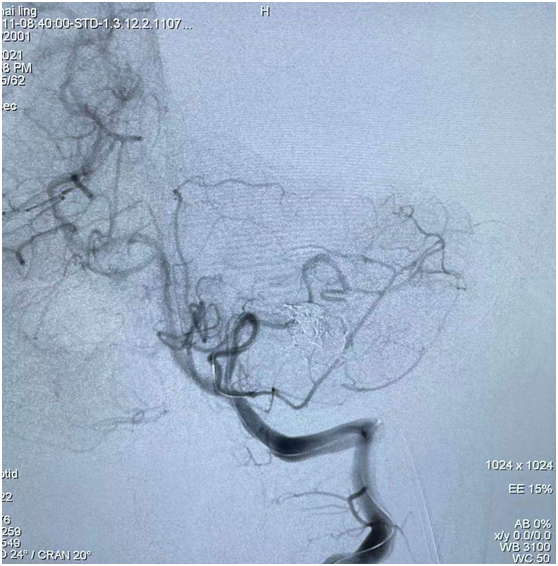

該患者因“突發(fā)頭痛、頭暈伴惡心嘔吐3天”入院,發(fā)病時就診當?shù)蒯t(yī)院,行頭顱CT顯示左側(cè)小腦出血,后轉(zhuǎn)我院進一步治療。在我院完善頭顱磁共振后考慮血管性疾病出血,給予全腦血管造影顯示左側(cè)小腦動靜脈畸形?;颊邽槟贻p女性,結(jié)合病情,家屬要求選擇創(chuàng)傷小、無手術(shù)疤痕的介入治療。神經(jīng)外科團隊積極完善術(shù)前準備,認真閱讀全腦血管造影圖像后制定了嚴密的手術(shù)方案。術(shù)中,科室團隊在傳統(tǒng)介入手法進行操作的基礎(chǔ)上,同時建立動脈及靜脈通道,動脈栓塞時因栓塞劑返流嚴重,立即采用備用方案經(jīng)靜脈途徑,由畸形團出口處反向注入栓塞材料,畸形團栓塞效果確切,完全未顯影,供血動脈及引流靜脈完好,基本達治愈效果?;颊咝g(shù)后神志清楚,無顱神經(jīng)受損癥狀,四肢活動正常,術(shù)后5天痊愈出院。

圖3:嘗試動脈途徑栓塞,栓塞劑返流嚴重